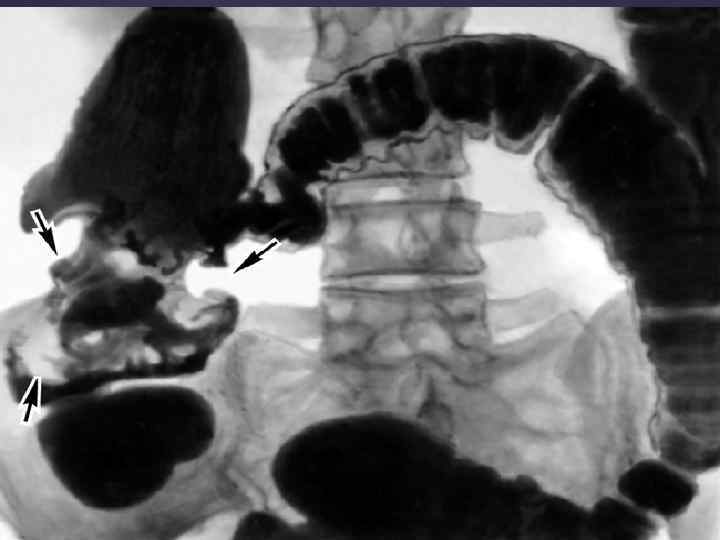

Ирригоскопия